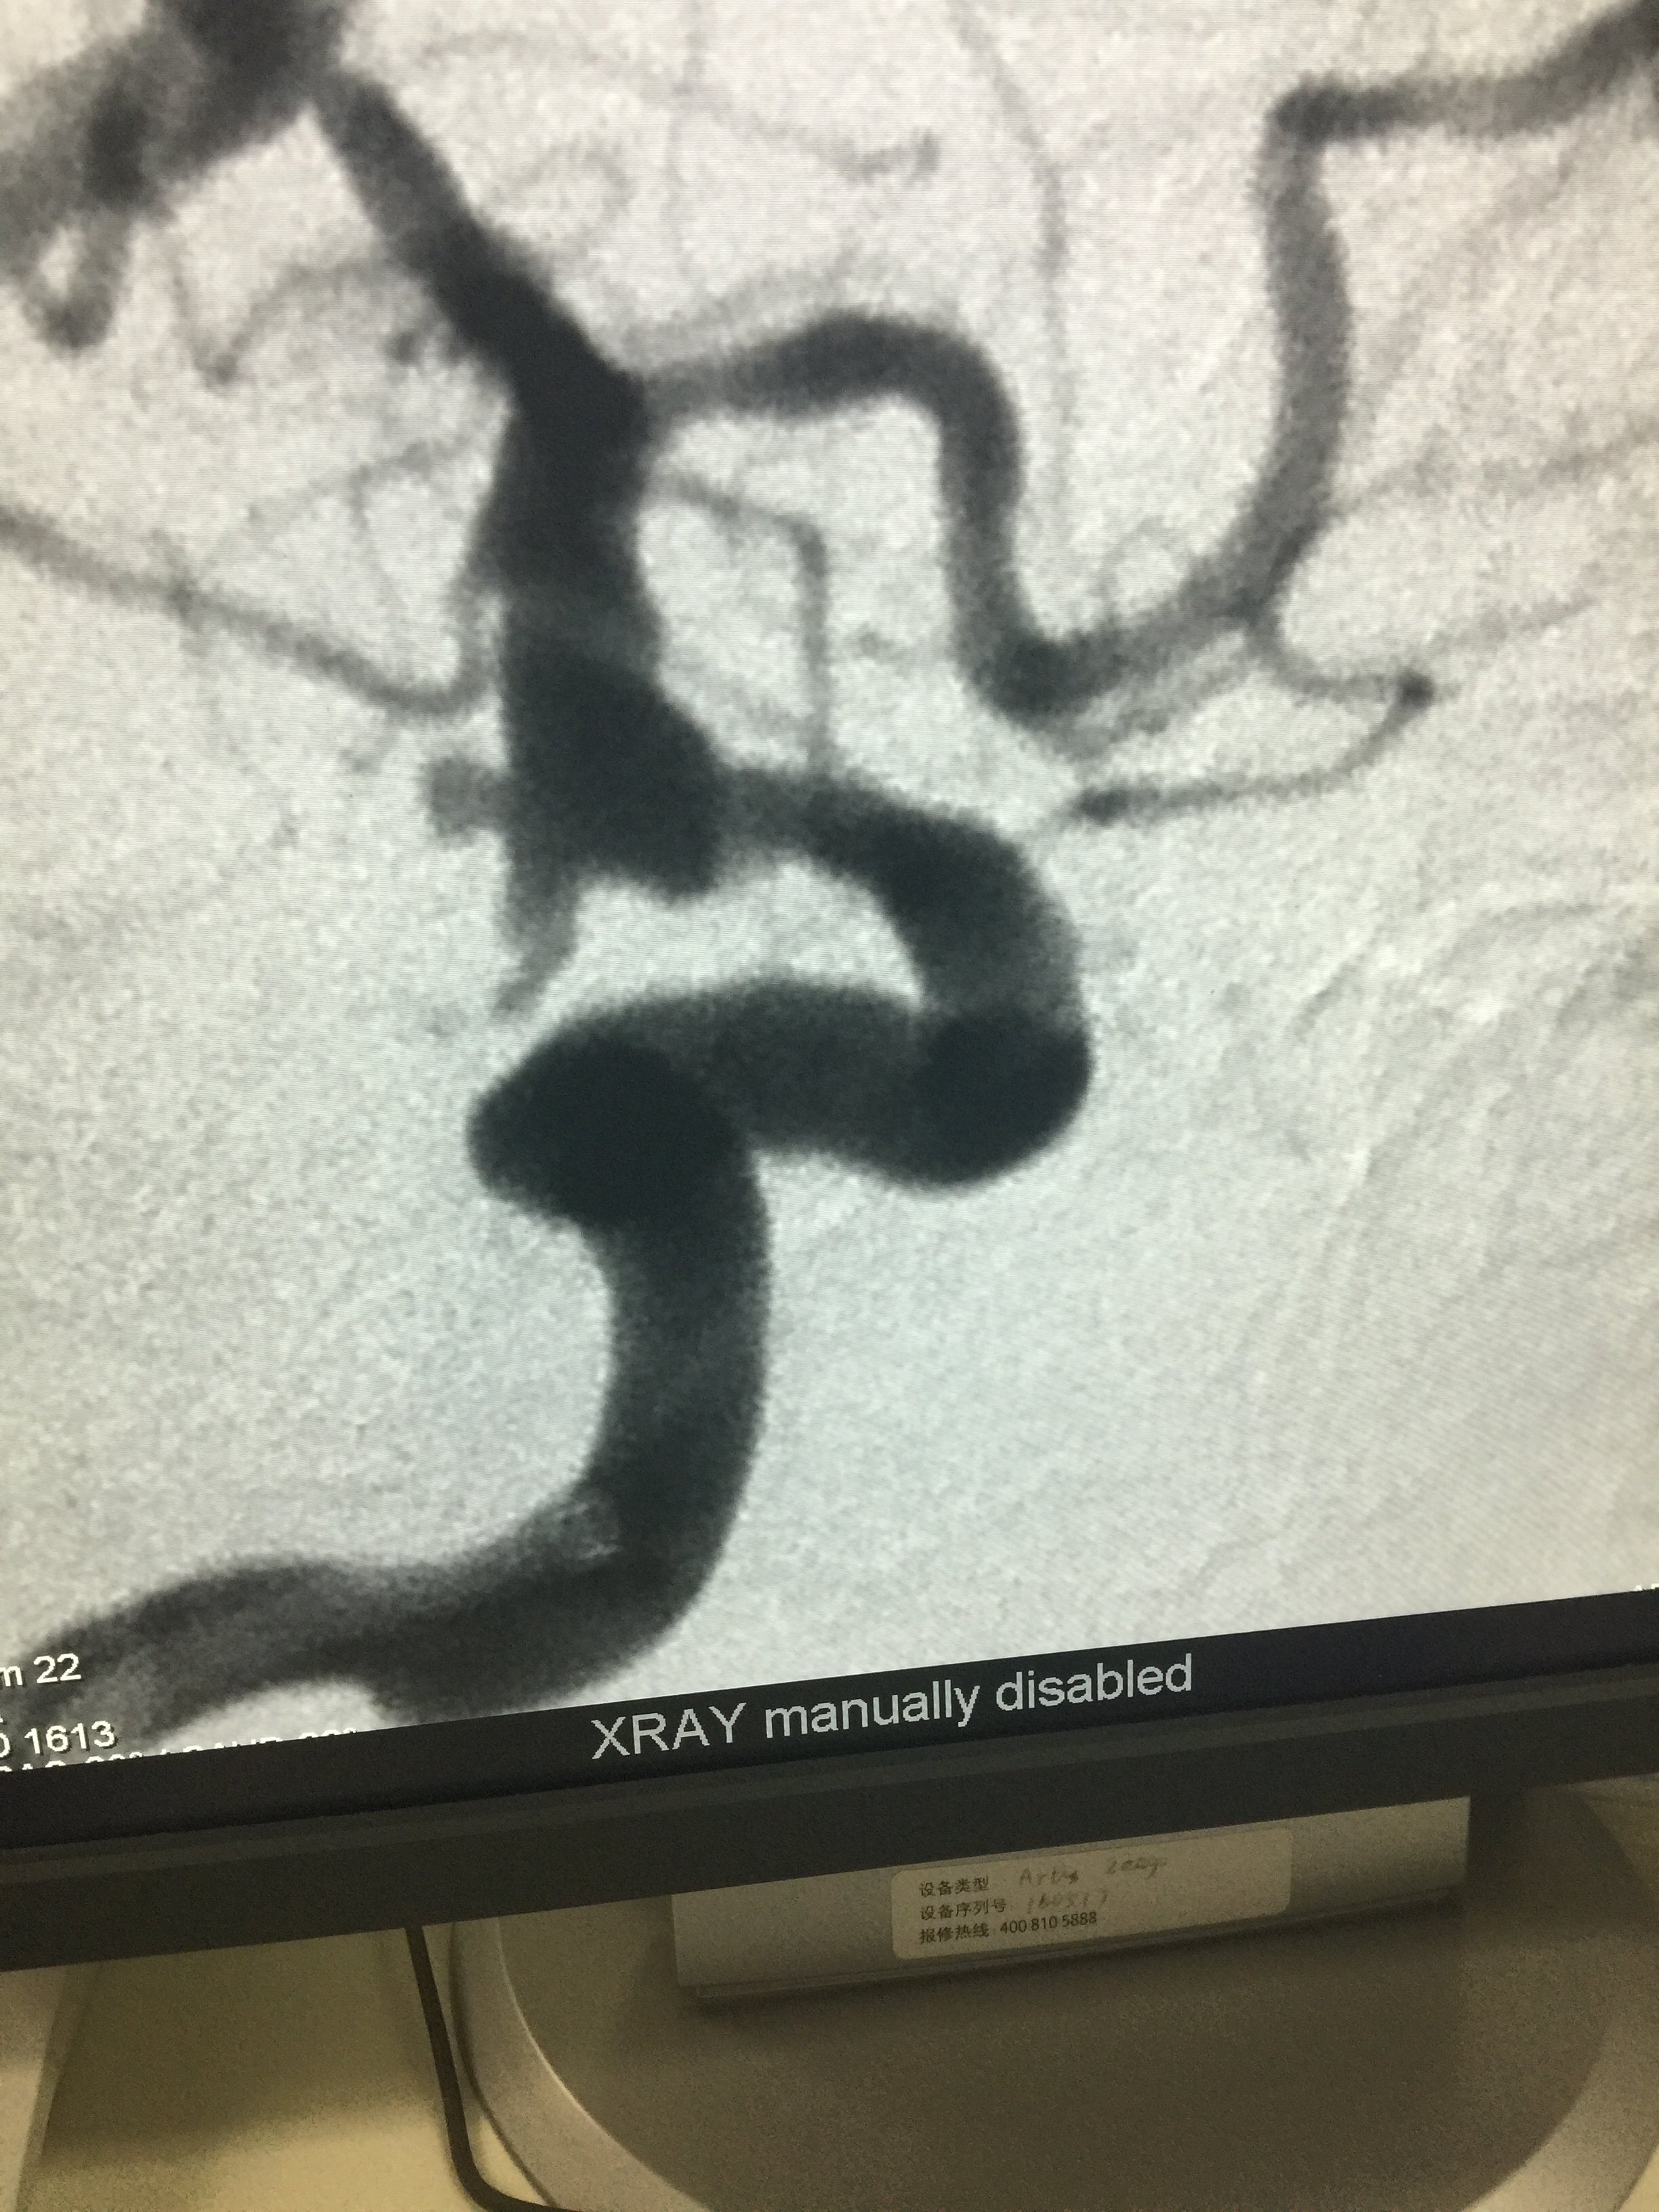

病例二:前交通动脉瘤-术前

1534032335.png

术后